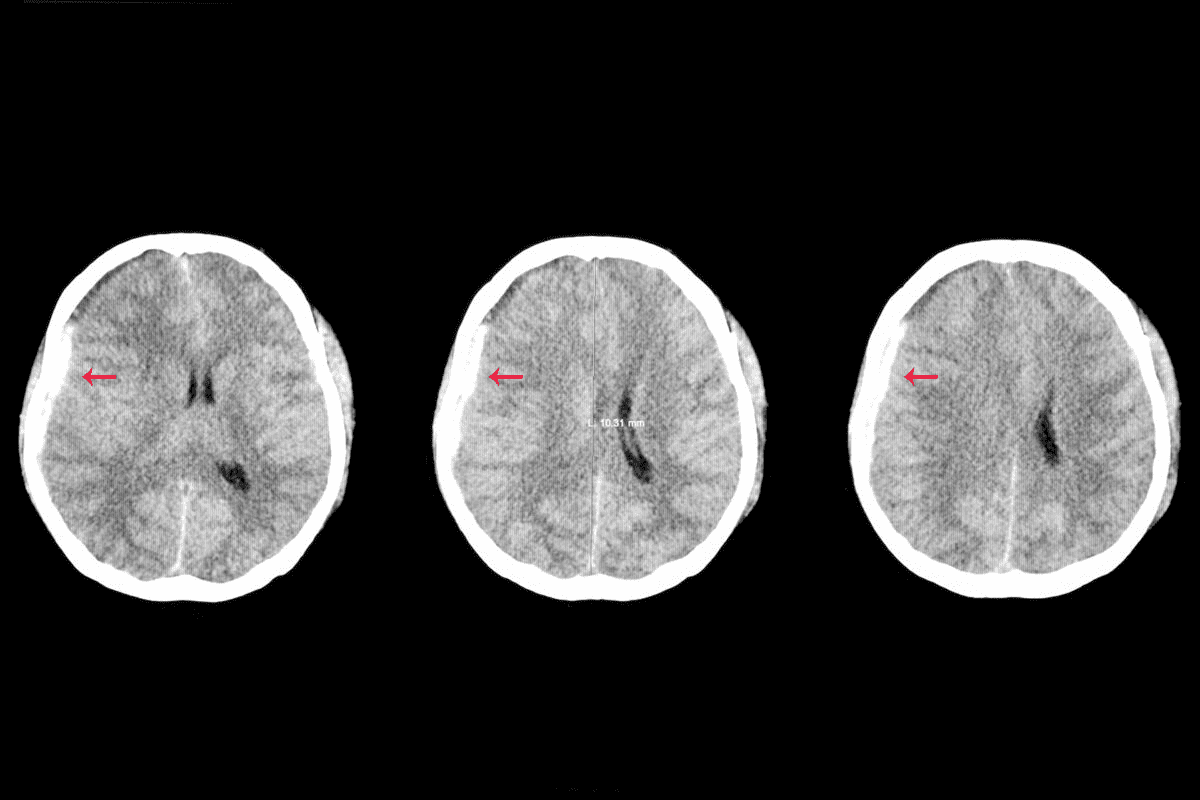

The Role of Imaging in Determining Prognosis

Imaging like ultrasound, CT scans, and MRI are very important. They help see how big the tumor is and if it has spread. This info helps doctors plan the best treatment and predict how well a patient will do.